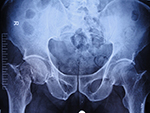

# NOF - CASE 3

Imm psop ap